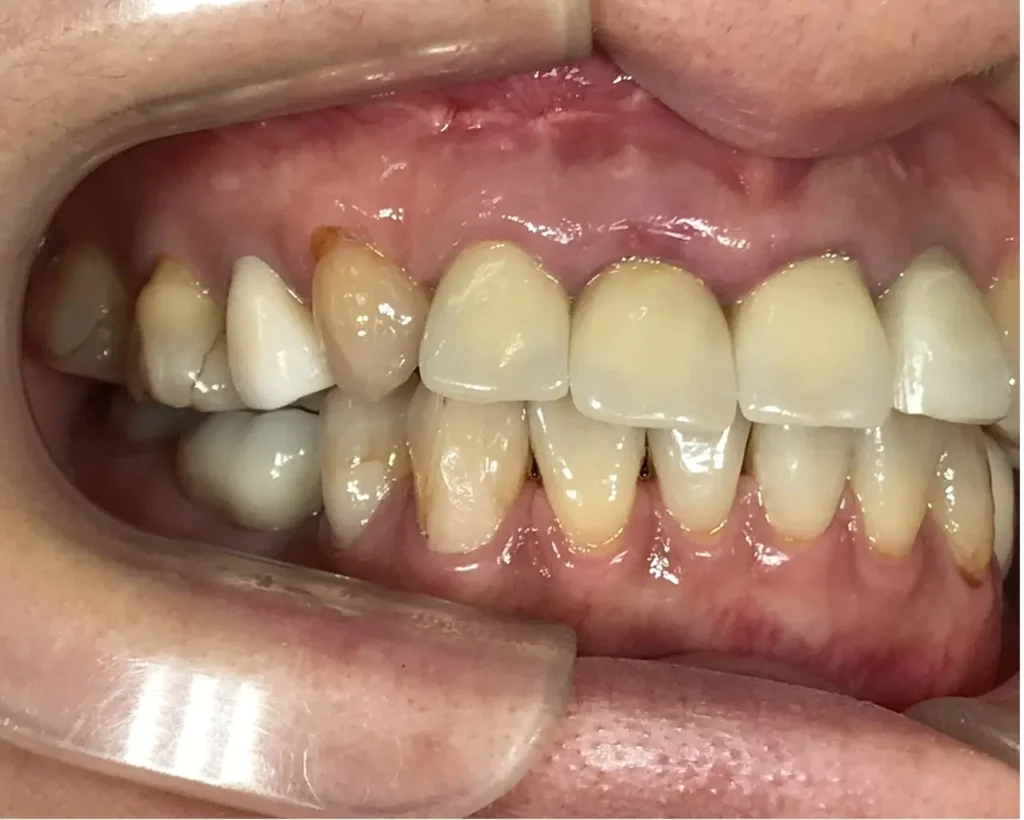

術後1年口腔内写真

外科的処置の跡はほとんどなく、ブリッジも自然な感じで歯がないようには見えません

治療の特徴

歯根破折は残念ながら抜歯しか方法はありません。外科的歯内療法は切開線が歯茎が下がったり、切開の跡が残ったりしますが、適切にデザインすればう甘く行くことがあります。今回は治療前とほとんど変わらず、歯肉の審美を損なわずにうまくいきました。